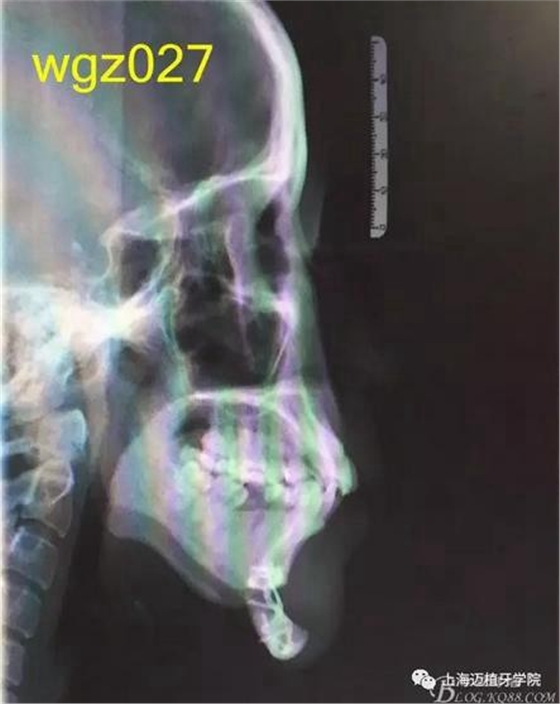

根據(jù)以下上傳的圖片及X線影像資料,你認(rèn)為她的牙齒存在什么問(wèn)題?應(yīng)該如何進(jìn)行矯治設(shè)計(jì)?

圖3

上海萬(wàn)眾醫(yī)院正畸科進(jìn)修醫(yī)生魏倩倩作業(yè)。 某女,25歲。 主訴:頦部術(shù)后自覺(jué)牙齒不齊,牙齒凸要求矯正。 既往史:曾有顳下頜關(guān)節(jié)疼痛史,于外院診斷為關(guān)節(jié)不可復(fù)性前移位伴髁突不對(duì)稱,行關(guān)節(jié)盤復(fù)位術(shù)。約3個(gè)月前在外院行頦成形術(shù),現(xiàn)因牙齒不齊,牙齒凸前來(lái)就診。 口外檢查:正面觀,長(zhǎng)面型,左右基本對(duì)稱,面下1/3過(guò)長(zhǎng),頦部明顯水腫,質(zhì)硬; 側(cè)面觀,面型稍凸。 顳合關(guān)節(jié)檢查:無(wú)壓痛,左側(cè)彈響,兩側(cè)髁突運(yùn)動(dòng)基本一致。 口內(nèi)檢查:恒牙列,下頜前庭處縫合,傷口愈合良好??谇恍l(wèi)生情況一般,牙齦紅腫,LR2、LL6缺失,UR456舌傾與LR67成反合關(guān)系,UR3頰側(cè)突出移位,UR2UL2近中扭轉(zhuǎn),UL1近中外翻唇傾,UR7UL7頰傾,LR6近中傾斜升高,LR5近中傾斜,LR4頰傾移位,LR3冠舌側(cè)傾斜,LL2近中扭轉(zhuǎn)冠頰傾,LL3舌傾,LL78近中傾斜。 模型分析:上頜前牙段擁擠度9.5mm,下頜前牙段擁擠度9mm,spee左右約3mm, LL5、LL7之間間隙約為5mm。上下中線右偏約1.5mm。全牙比約為80%,前牙比62%。磨牙關(guān)系:右側(cè)近中關(guān)系,UL6與LL7遠(yuǎn)中尖對(duì)尖。尖牙關(guān)系:右側(cè)遠(yuǎn)中關(guān)系,左側(cè)近中關(guān)系。 行為分析:患者已于外院行頦成形術(shù),面型已改善,但患者仍覺(jué)得牙齒凸,說(shuō)明患者非常重視面型問(wèn)題,對(duì)美觀要求高。 頭顱側(cè)位片:面型稍凸,上唇在E線前約1.5mm,下唇在 E前約1mm 。 SNA: 85↑ SNB: 75↓ANB: 10↑ U1-L1: 113.6↓ U1-SN: 107.9 L1-M P: 88 ↓Y軸角:65.8 FH-MP: 37↑ SN -M P: 45↑ 曲面斷層片:28顆恒牙,LL6缺失,牙槽骨均位于釉牙骨質(zhì)界以下,LR6、LL7近中牙槽骨角型吸收,頦部可見(jiàn)成型術(shù)鈦合板。左側(cè)升支較右側(cè)粗。 關(guān)節(jié)片:左右髁突不對(duì)稱,髁狀間隙右側(cè)明顯較左側(cè)寬,右側(cè)間隙清楚,大小勻稱 ,左側(cè)欠佳。 診斷:安氏3類 骨性2類 高角 上下前牙重度擁擠 中線不齊 間隙分析:下頜 , LL5與LL7之間的有5mm間隙,下頜擁擠度為9mm,整平下頜曲線需要約3mm間隙,下頜需要約12mm間隙,減去現(xiàn)有間隙還需要7mm間隙。上頜,擁擠度為9.5mm,擁擠主要集中在前牙段。 支抗分析:患者頦部術(shù)后仍覺(jué)面型凸(主要是上頜前突),所以除了要解決擁擠度外還需要內(nèi)收前牙,所以上頜需要強(qiáng)支抗?;颊逽NB為75,下頜發(fā)育不足,高角,相對(duì)低角病例來(lái)說(shuō),下頜磨牙較易前移。下頜前牙重度擁擠的情況下主張只解除擁擠不宜內(nèi)收(該患者系下頜后縮病例)。患者ANB為10°,本屬于正頜正畸聯(lián)合治療,現(xiàn)患者已做頦部成型術(shù),患者面型得到改善,故患者現(xiàn)在主要為解決擁擠,少量?jī)?nèi)收前牙,解決上前牙凸度。